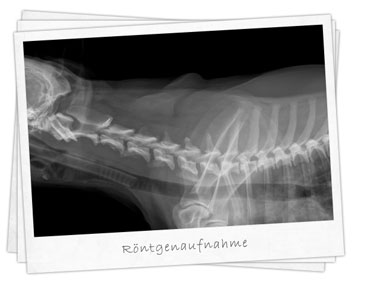

Röntgenaufnahme

Wirbelsäulen- und Gelenktherapie nach Dorn:

• Sanfte Technik zur Mobilisation

• Bei Gelenkblockaden

• Bei Blockaden der Wirbelsäule